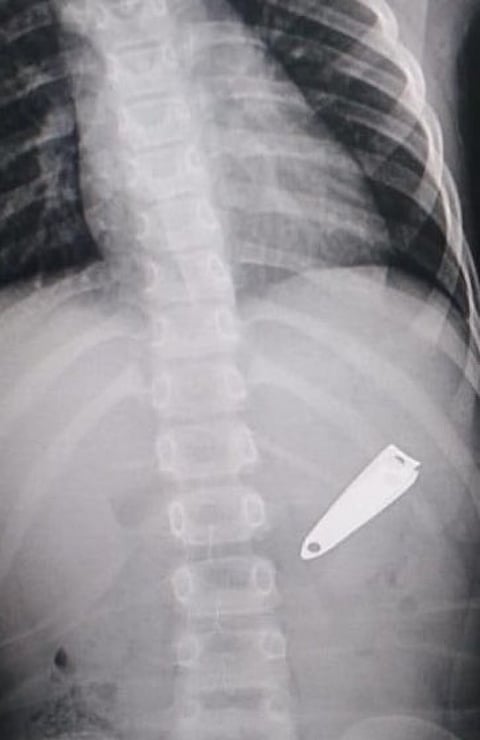

تمكّن فريق طبي بمستشفى الولادة والأطفال ببريدة، عبر تقنية المنظار، من استخرج مقص أظافر من بطن طفلة تبلغ من العمر 4 سنوات، بعد أن ابتلعته وعلِق في بطنها.

وبعد وصولها المستشفى كانت الطفلة تعاني من الألم، ليتم الكشف عليها فورًا لإنقاذ حياتها، فاتضح وجود جسمٍ غريب ظهر فيما بعد أنه "مقص أظافر"، ورغم صعوبة العملية واحتمالية وجود مضاعفات استطاع الفريق الطبي استخراجه واستقرّت حالة الطفلة.